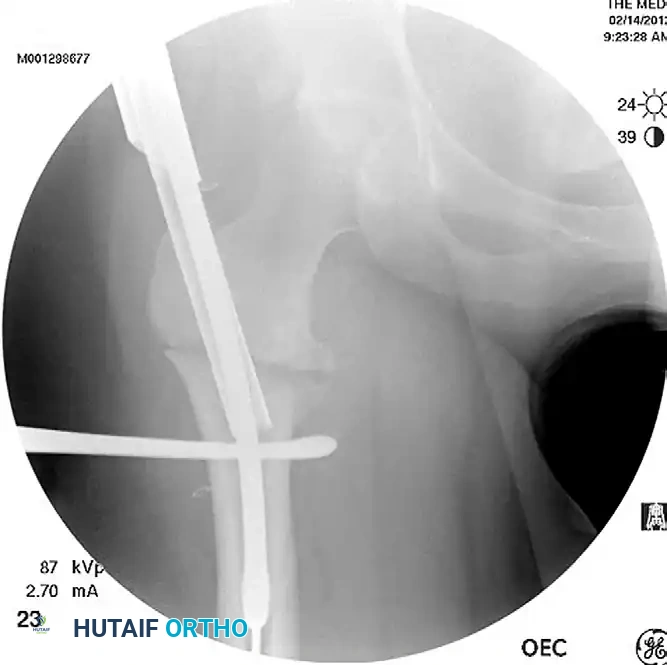

Image

Preoperative radiograph demonstrating a displaced subtrochanteric femoral fracture with characteristic proximal fragment abduction and flexion.